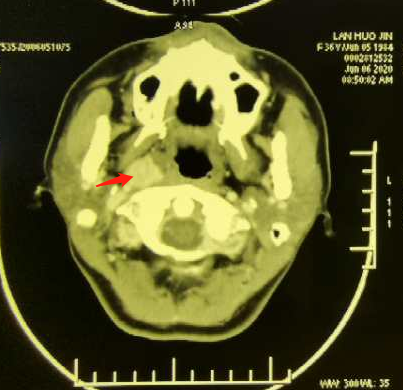

病例二

36岁年轻女性,发现颈前肿物半个月,诊断甲状腺癌双颈,右咽旁转移,咽旁转移淋巴结罕见,位于颈内动脉及静脉前方近颅底处,周围有重要的神经,一旦出血难以控制,手术难度大。